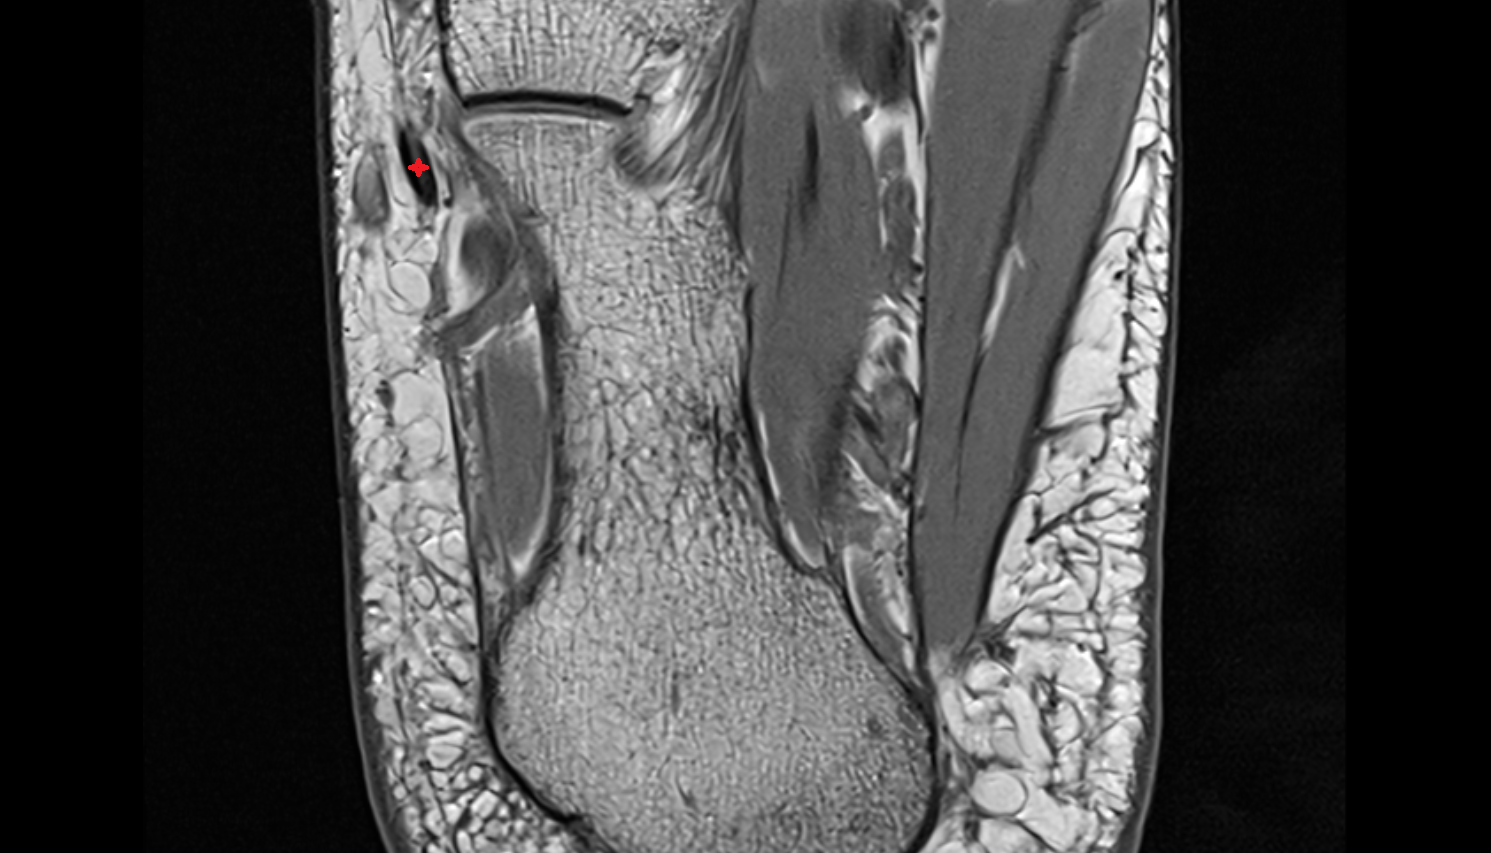

- Temporomandibular joint

- Mandibular condyle

- Mandibular fossa

- Superior head of lateral pterygoid muscle

- Inferior head of lateral pterygoid muscle

- Lateral pterygoid muscle

- Temporalis muscle